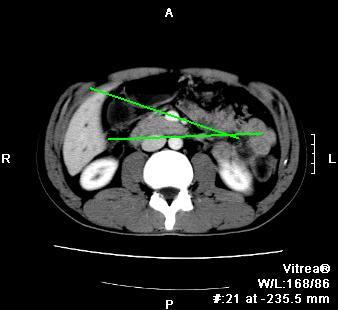

以下是引用听蝉观竹在2008-4-26 14:21:00的发言:[br]这个病例许多人认为“胰头增大”,那么到底胰头增大的标准是什么呢?

以下是引用听蝉观竹在2008-4-27 10:10:00的发言:[br]关于胰头大小问题有几种测量方法和正常值:[br][br]1、直量法:横径<4cm;[br]2、胰头横径与相邻层面椎体横径的比值为二分之一,超过椎体横径就提示胰头增大;[br]3、正常组成年人肠系膜上动、静脉水平夹角正常值范围为4.9°~34.7°大于35°提示胰头增大。[br][br]上述方法只是一种具体的判断,是“量”的评估,更重要的是“质”的评估:一是观察边缘是否光滑,有无局部隆起,有无分叶;二是观察密度(增强,尤其在动脉期和门脉期)是否均匀。[br][br]所以对于胰头是否有异常不仅仅是是目测可以解决问题的,不要轻易就说“胰头增大”。还有一个问题就是测量胰头应该在增强ct上进行,这样可以避免将血管测量进去。[br][br]为什么啰嗦讲怎么多,因为我们实际工作中同样存在影像科医生和临床医生动不动就说胰头增大,说是胰头癌。大家看看是不是这种情况?[br][br] 我个人观点-----本病例的胰头不增大。[br][br][本贴已被 听蝉观竹 于 2008-4-27 10:12:41 修改过]